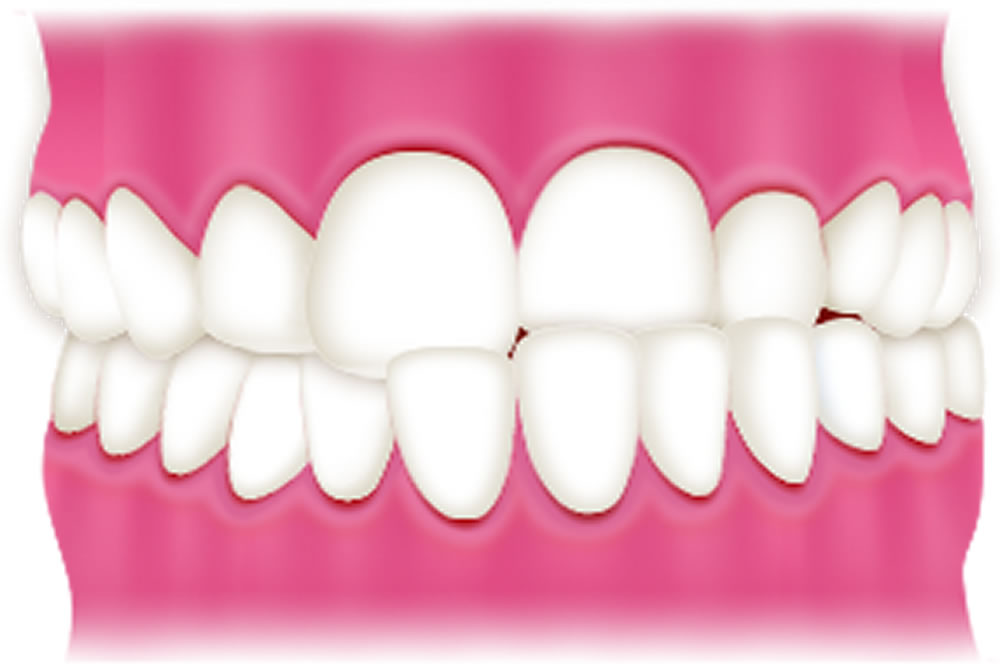

過蓋咬合

上顎の歯が下顎の歯を大きく覆うほど、咬み合わせが深い状態です。前歯で噛みにくく奥歯や顎に負担がかかるため、奥歯の喪失や顎関節症のリスクが高まります。また、下の前歯が上の歯茎を傷つけることがあります。